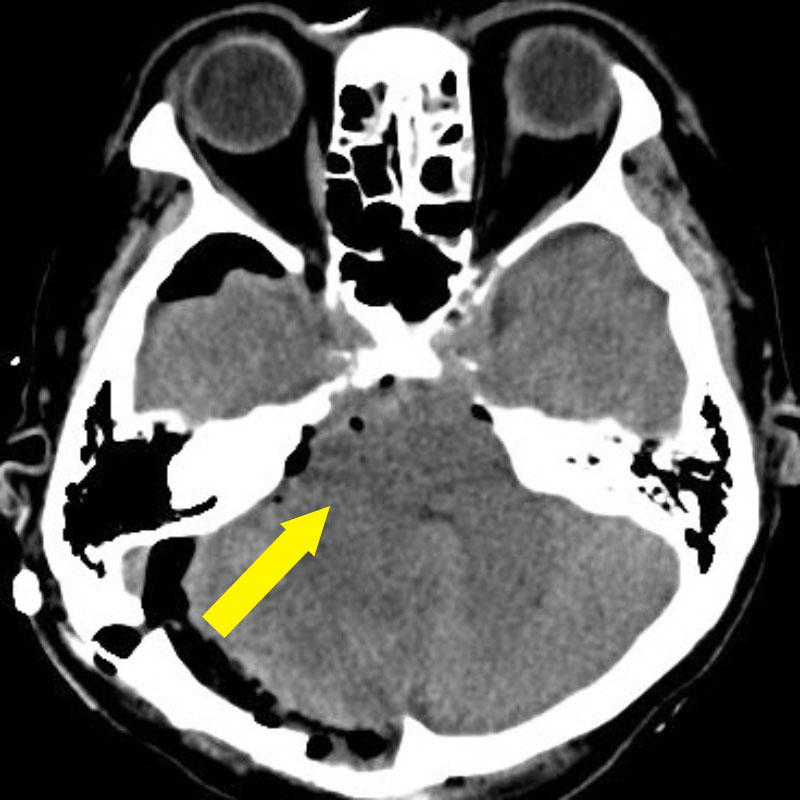

'25年1月

50代

南田,野本

右小脳

出血性海綿状血管腫

再出血の予防目的

兵庫県の病院

より紹介

No.No.59 手術前1

No.No.59 手術前2

No.No.59 手術後1

No.No.59 手術後2

CT/MRにより完全に摘出されたことが確認された